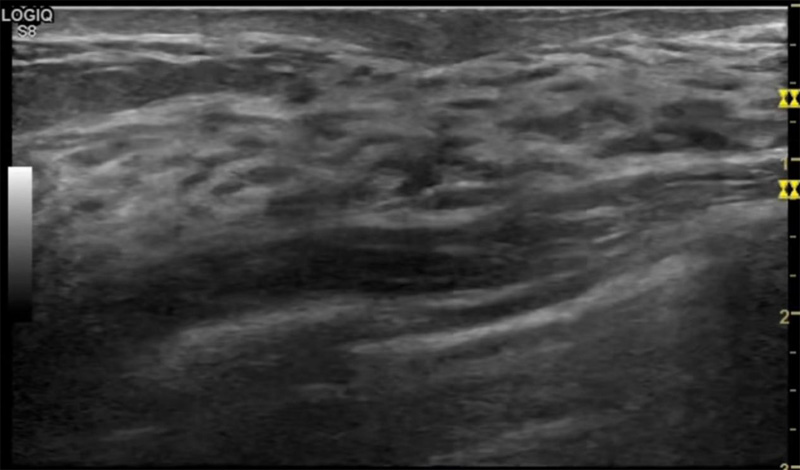

乳腺病變最常用的檢查方法乳腺超聲設備發揮作用

乳房脹痛,觸摸疼痛,手摸起來感覺有腫塊。這個是什么問題呢?醫生診斷一般是乳腺增生。那么在乳腺超聲設備檢查后,報告單卻顯示雙乳未見明顯占位性病變。乳腺增生是很多女性,特別是育齡期女性都有的經歷、到底乳腺增生癥狀有哪些?會給我們帶來怎樣的影響呢?乳腺增生不是腫瘤跟炎癥。乳腺組織增生及退行性變跟內分泌功能紊亂有關系。正常的生理改變。還有乳腺病,良性乳腺結構不良等名稱。

乳腺增生有什么癥狀,病因?比較典型的就是乳房疼痛,特別是經前癥狀比較重,經后就有所緩解。有時候還能碰到乳房硬塊。根據經期的變化而變化硬度大小都有變。乳腺在內分泌激素,伴隨月經周期有增生問題。內分泌激素代謝失衡,雌激素水平增高,出現乳腺組織增生過度,增生組織不退的情況下,就會有乳腺增生癥狀。這個不會增加乳腺癌的風險。所以不用緊張的。不過乳腺癌的病人都會有乳腺增生。所以乳腺增長有沒癥狀,都需要進行常規的體檢。

乳腺超聲設備便捷安全的檢查方法,國際上有乳腺檢查超聲的指南??梢葬槍θ橄偌膊∽龀鱿到y的分類。《乳腺超聲若干臨床常見問題專家共識(2018版)》說明不建議提示乳腺增生癥。單純的囊腫,乳腺改變等。在BI-RADS分類中已經納入不同類別。針對未發現占位的乳腺,雙乳未見占位性病變(BI-RADS 1類)。因此看到這樣的檢查報告時候,不用緊張擔心,占位性結節沒有形成。